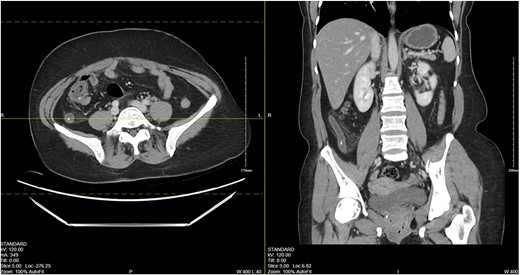

CT imaging showed an appendix dilated to 13 mm with wall thickening, periappendiceal induration and appendicoliths (Fig. 1).

CT abdomen/pelvis showing a dilated appendix with wall thickening, periappendiceal induration and appendicoliths.